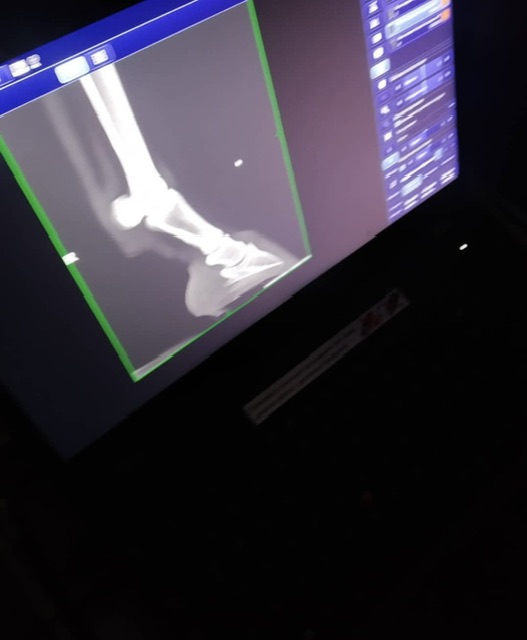

Мерин 8 лет, хромает 2 года (снимки сделаны 2 года назад

Кто может подсказать диагноз? Правая передняя нога